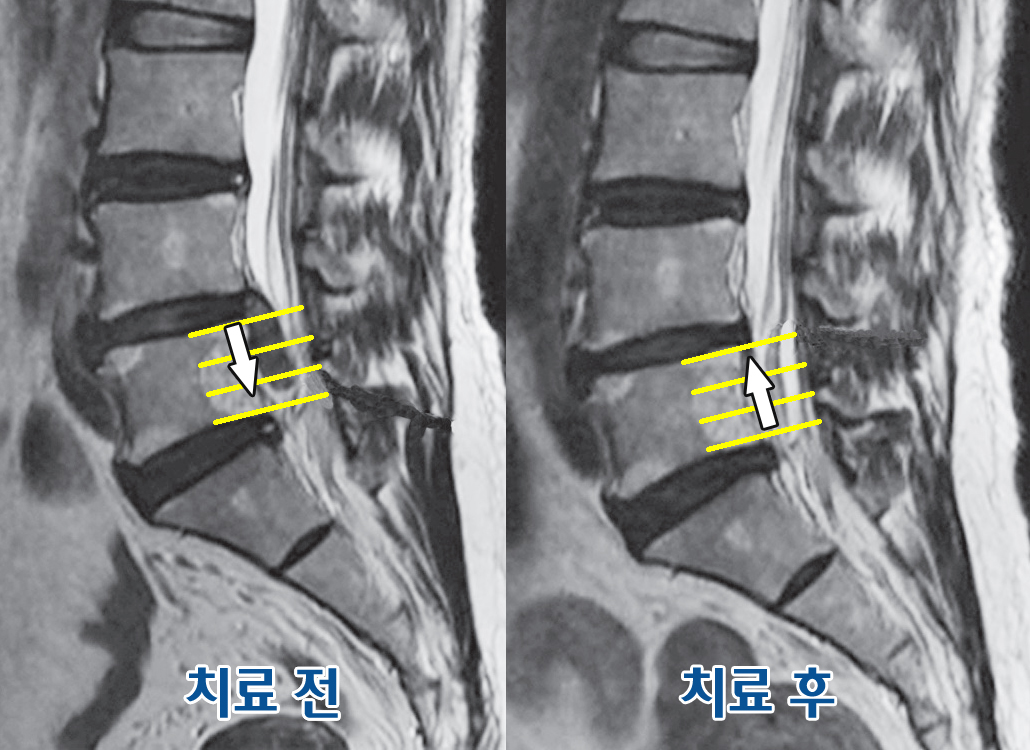

허리디스크는 현대인에게 매우 흔한 문제이며, 이를 통해 다양한 증상이 나타날 수 있습니다. 허리디스크, 즉 추간판 탈출증은 척추 디스크가 돌출되거나 파열되어 신경을 압박하게 되는 상황을 말합니다. 이로 인해 통증과 불편함이 발생하며, 일상생활에 큰 지장을 줄 수 있습니다.

마지막으로, 시간이 지나도 증상이 개선되지 않고 만성화되거나 심해지고 있다면, 반드시 적절한 전문의를 찾아가야 합니다.

마지막으로, 허리디스크 증상이 나타날 경우 무리하게 활동하거나 자가 치료를 하기보다는 전문가의 진단을 받는 것이 중요합니다.